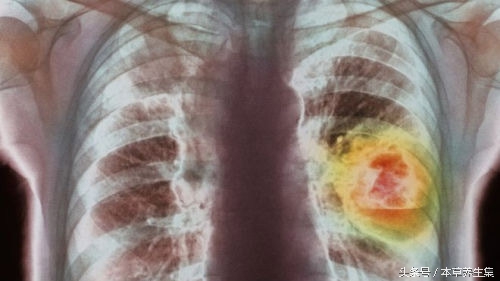

肺癌的形成是一个非常复杂的过程,简单的来说:各种各样的有害物质直接或间接作用于人体,比如吸烟、空气污染、经常接触修建柏油马路的沥青、石棉、各种射线、反复气管或肺部感染等,引起基因突变,导致肺部内正常的细胞变成肿瘤细胞,这样便形成了肺癌。

中医认为,肺癌多由于正气内虚、邪毒外侵而引起,以痰浊内聚,气滞血瘀,蕴结于肺,而致肺失宣降为基本病机,以咳嗽、咯血、胸痛、发热、气急为主要临床表现的一种恶性疾病。